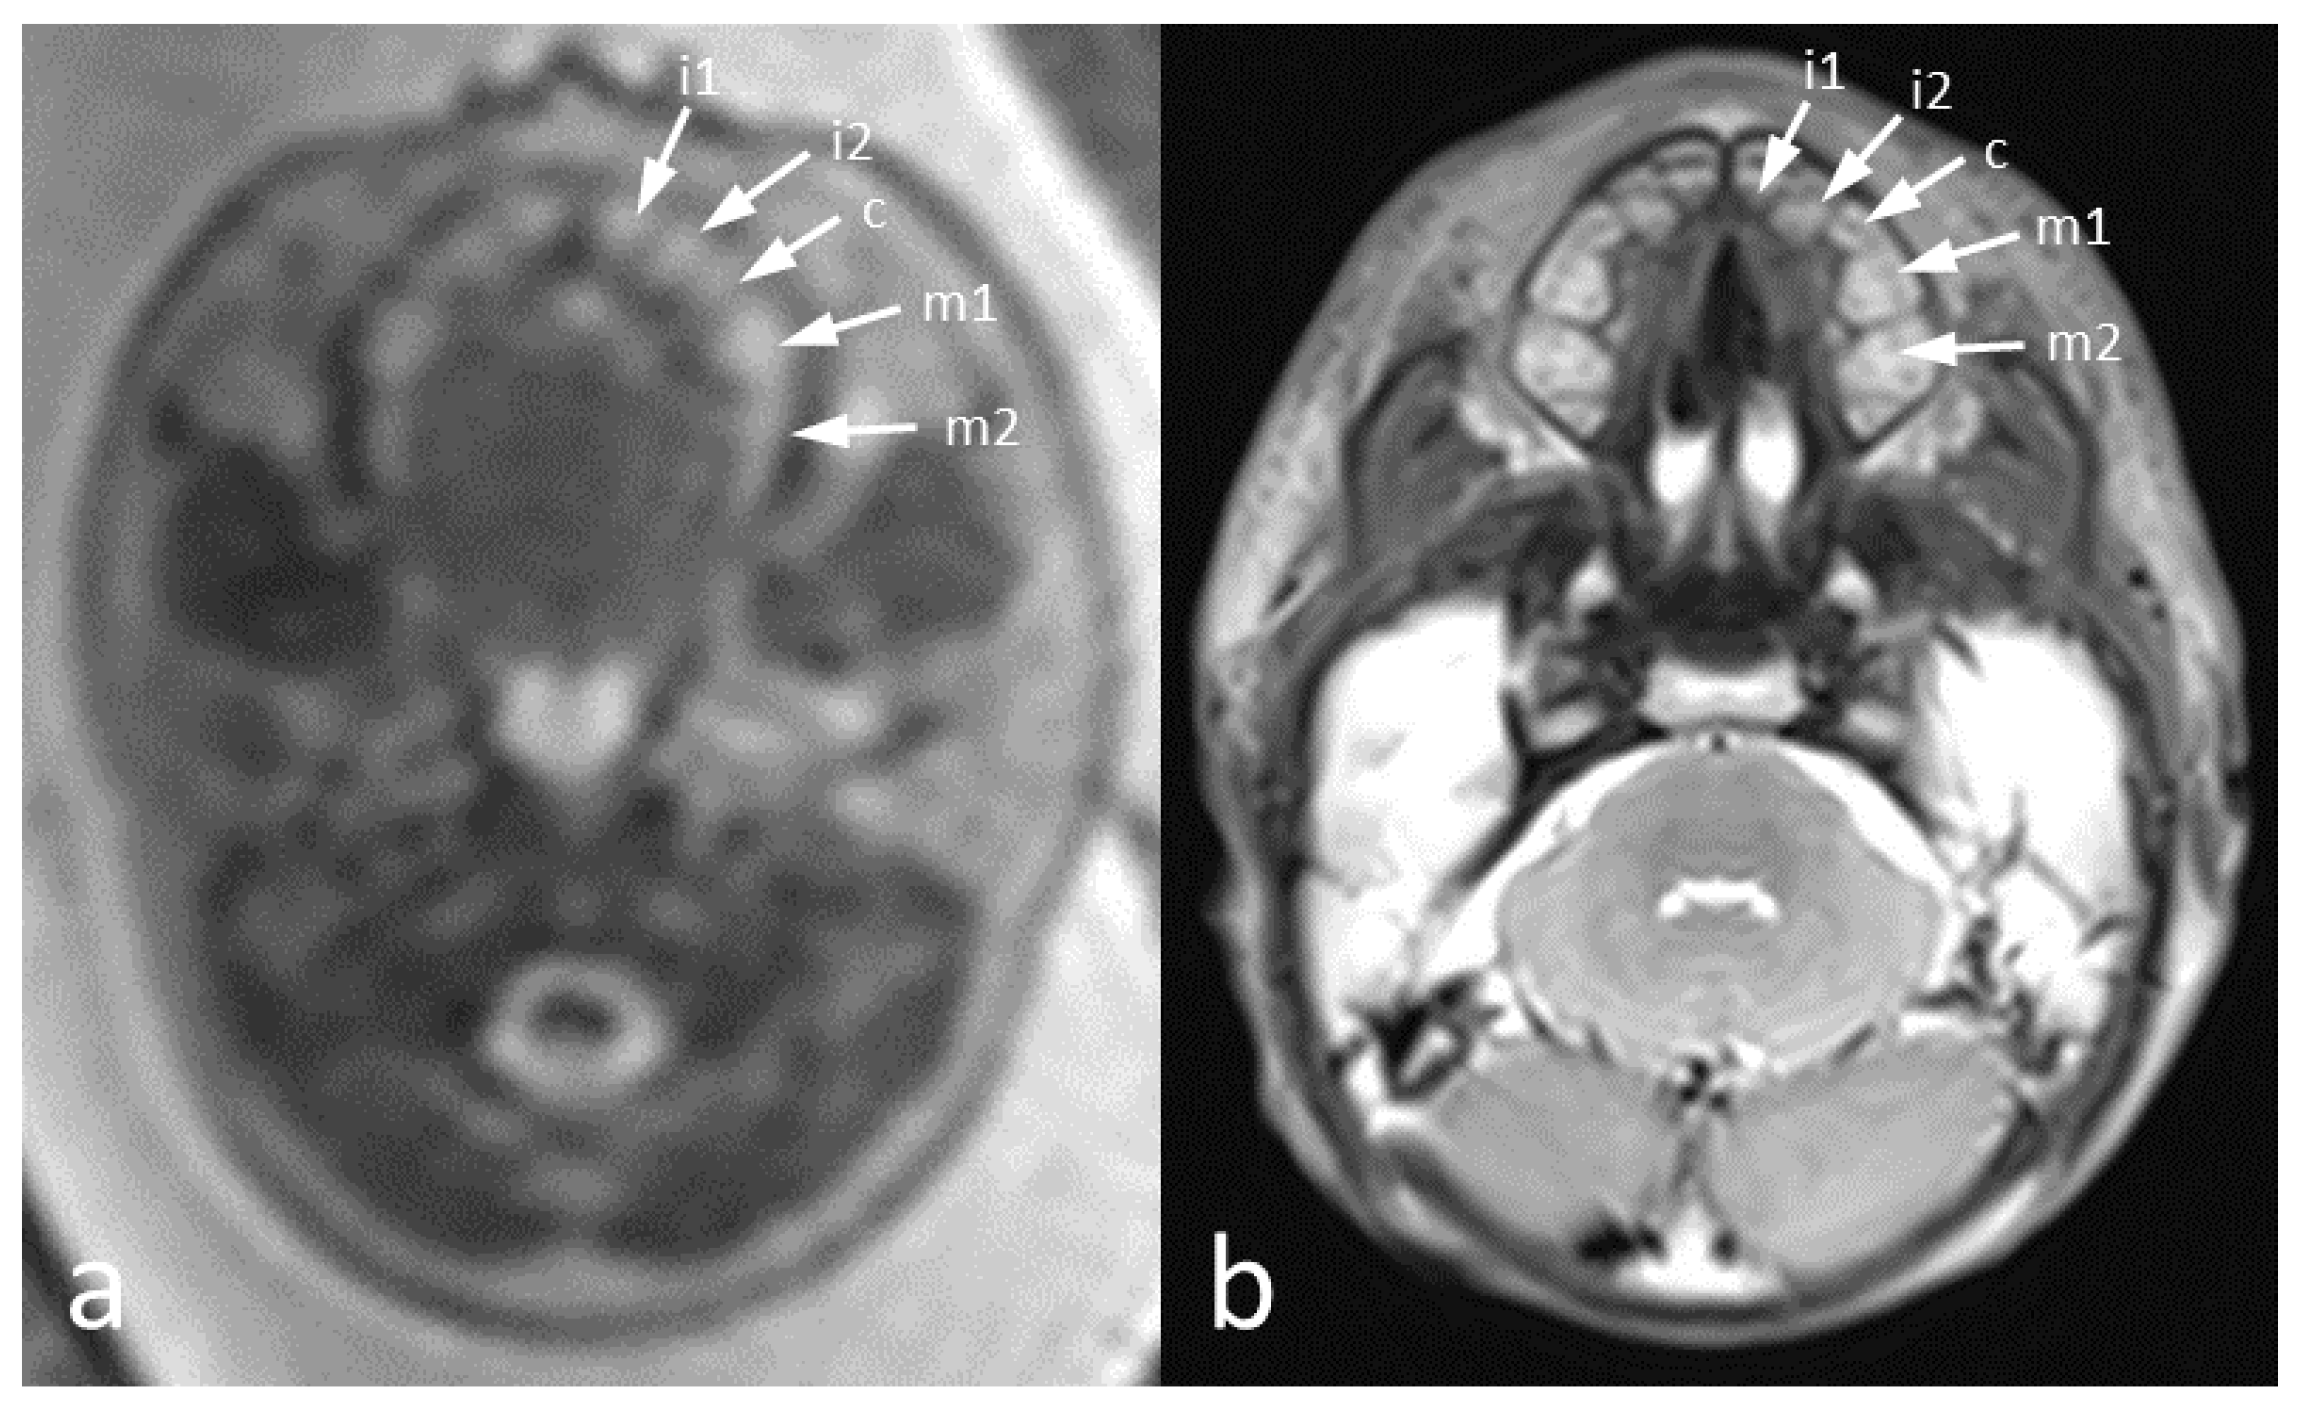

- Mailath-Pokorny, M.; Klein, K.; Worda, C.; Weber, M.; Brugger, P.C.; Czerny, C.; Nemec, U.; Prayer, D. Maxillary dental arch biometry: Assessment with fetal MR imaging. Prenat. Diagn. 2012, 32, 530–535. [Google Scholar] [CrossRef]

- Victoria, T.; Johnson, A.M.; Edgar, J.C.; Zarnow, D.M.; Vossough, A.; Jaramillo, D. Comparison Between 1.5-T and 3-T MRI for Fetal Imaging: Is There an Advantage to Imaging with a Higher Field Strength? AJR Am. J. Roentgenol. 2016, 206, 195–201. [Google Scholar] [CrossRef]